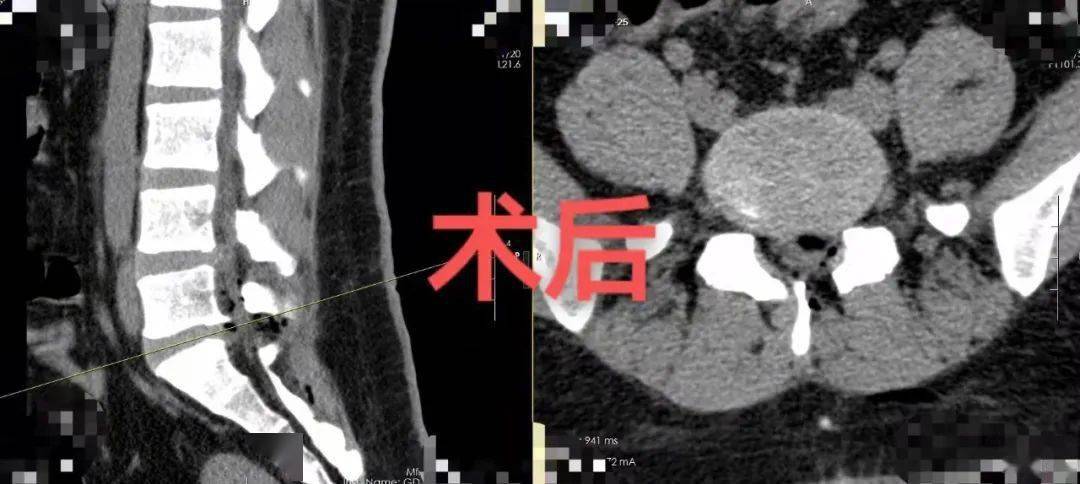

该院接诊的神经外九科主任穆林森仔细询问病史并查看相关的影像检查资料 , 发现患者腰4/5椎间盘明显向后突出 , 腰5/骶1椎间盘明显向左后突出并伴有部分脱落 , 相应的椎管明显变窄 , 神经压迫明显 。 完善术前检查后 , 11月5日 , 穆林森团队为患者实施了微创腰椎间盘突出切除术 , 顺利解除了神经根压迫 。

术后第三天 , 肖坤已经能下床自行运动锻炼 。 术后给予康复等对症治疗后 , 肖坤于近日出院 。